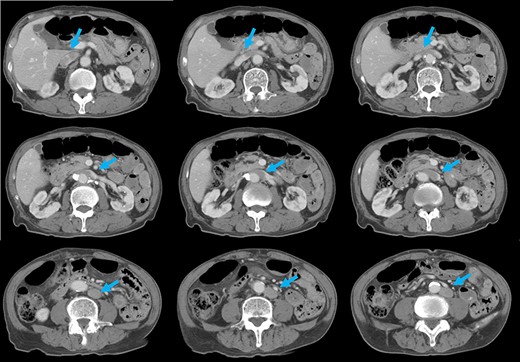

Preoperative computed tomography (CT) revealed a tumor in the sigmoid colon accompanied by some regional lymph node swelling (Fig. 1). It also showed that the IVC ascended vertically along the left side of the abdominal aorta. After connecting with the left renal veins, the left-sided IVC crossed the abdominal aorta anteriorly to join the normal prehepatic segment of the IVC (Figs 2 and 3). Coronal CT showed that the descending colon misplaced at the abdominal midline and the sigmoid colon in the right upper abdomen (Fig. 4). The preoperative diagnosis was thus sigmoid colon cancer with left-sided IVC and PDM.

CT shows that, after connecting with the left renal veins, the left-sided IVC (arrows) crosses the abdominal aorta anteriorly to join a normal prehepatic segment of the IVC.